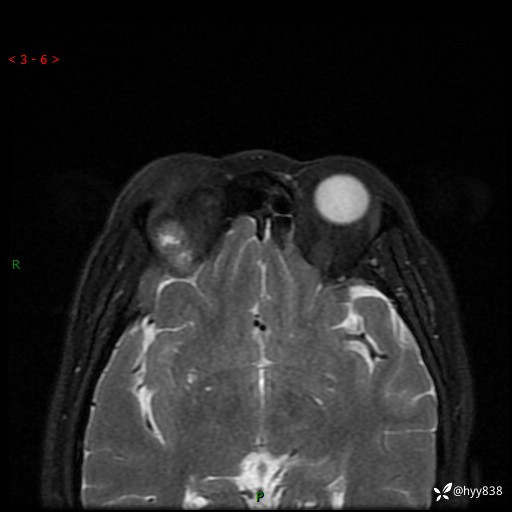

老年女性,右眼球突出1月。说说鉴别诊断,看谁第一个秒---(有结果)

主诉:发现右眼球突出1月余

简要病史:患者于1月前无明显诱因发现右眼球突出,偶感磨痛、眼胀,无视力下降,无头痛,恶心呕吐等不适。10天前就诊于当地县人民医院就诊,完善头颅ct检查,诊断为右侧眼眶肿物,建议患者上级医院进一步治疗,患者因个人原因拒绝。拟行手术,来我院就诊,门诊行相关检查后以“右眼眼眶肿物”收入院。 患病以来,患者精神饮食睡眠尚可,大小便如常、体重无明显改变。

辅助检查:MRI

临床诊断:眼眶肿物

眼眶MRI平扫+增强